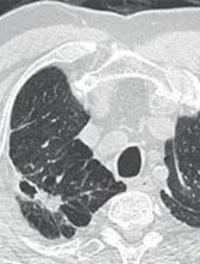

Asthme sévère hyperéosinophilique

L’asthme hyperéosinophilique est un phénotype d’asthme sévère bénéficiant de nouvelles options thérapeutiques. L’exploration complète d’un asthme hyperéosinophilique est un préambule indispensable afin d’éliminer les autres pathologies respiratoires comportant à la fois une hyperéosinophilie et des manifestations asthmatiques ou pseudo-asthmatiques. Les stratégies thérapeutiques actuelles font appel aux biothérapies, notamment aux anti-IL5.